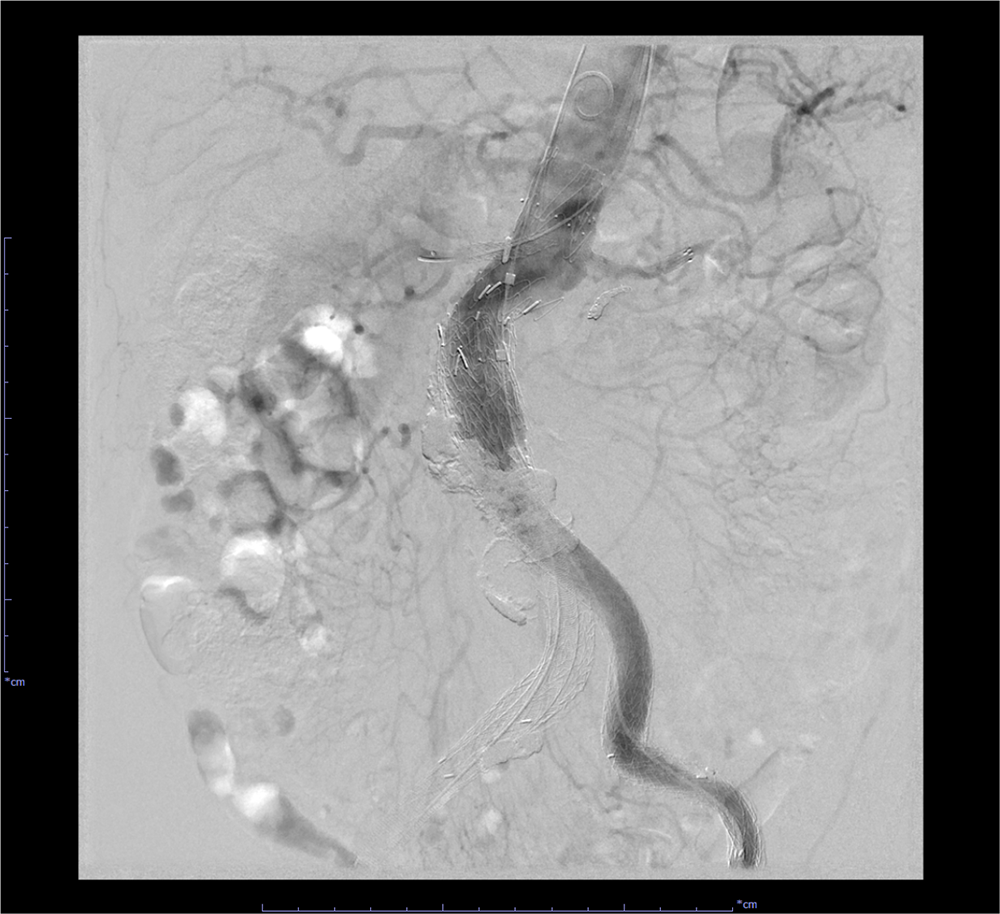

EVAR後の腹部大動脈瘤破裂に対し追加EVARを施行した一例

当科で腹部大動脈瘤に対しEVAR術後、瘤増大傾向で外来フォローアップされていた。急激な腹痛で来院し造影CTが撮影された。瘤内にType1aエンドリークを認めるほか、瘤内解離、破裂を認めた。緊急で追加EVARが行われ、治療後エンドリークは消失し、術後経過も問題なく退院となった。